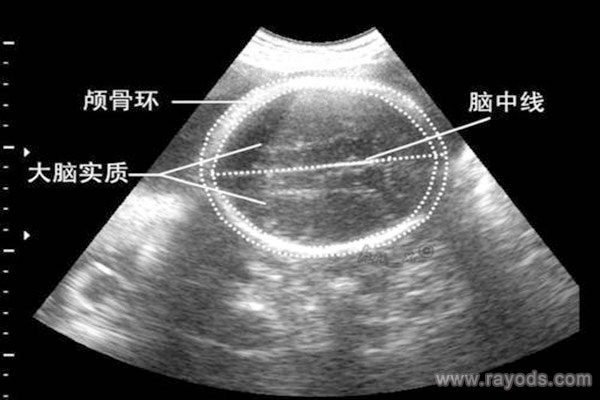

双顶径与孕周对照表,你家宝宝达标了吗?双顶径与孕周对照表双顶径是所有孕妈妈都熟悉的。主要是指胎儿头部最宽处从一侧到另一侧的长度。医生通过B超可以清楚的看到宝宝的双..